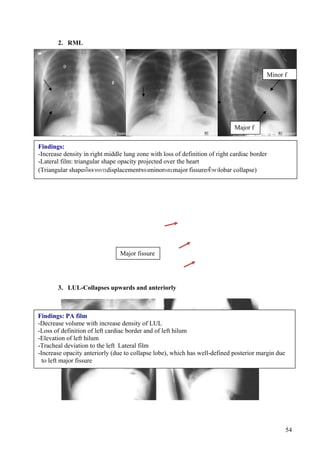

2. RML

Minor f

Major f

Findings:

-Increase density in right middle lung zone with loss of definition of right cardiac border

-Lateral film: triangular shape opacity projected over the heart

(Triangular shapeเกิดจากการdisplacementของminorและmajor fissureเขาหาlobar collapse)

Major fissure

3. LUL-Collapses upwards and anteriorly

Findings: PA film

-Decrease volume with increase density of LUL

-Loss of definition of left cardiac border and of left hilum

-Elevation of left hilum

-Tracheal deviation to the left Lateral film

-Increase opacity anteriorly (due to collapse lobe), which has well-defined posterior margin due

to left major fissure